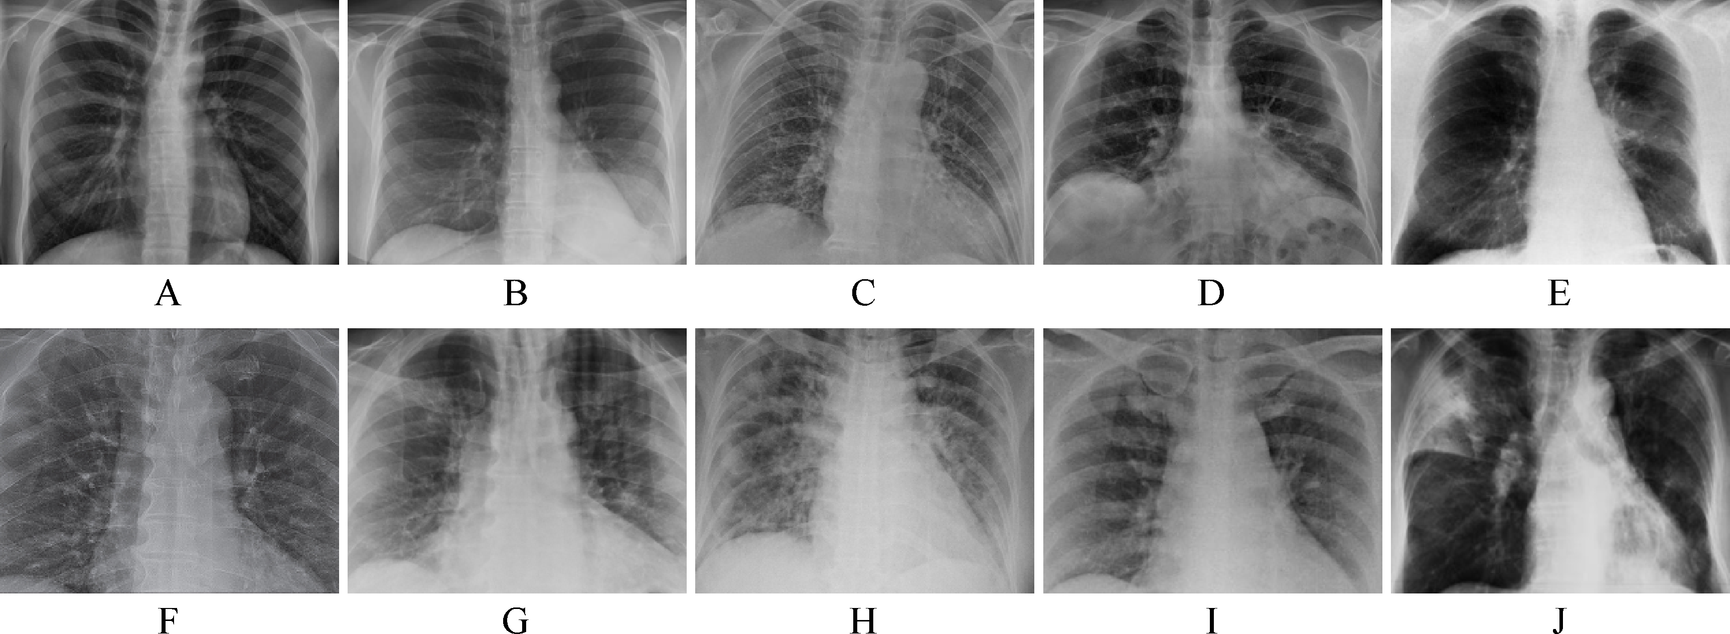

Representative COVID-19 lung X-ray image used as input for segmentation (not the output)25.